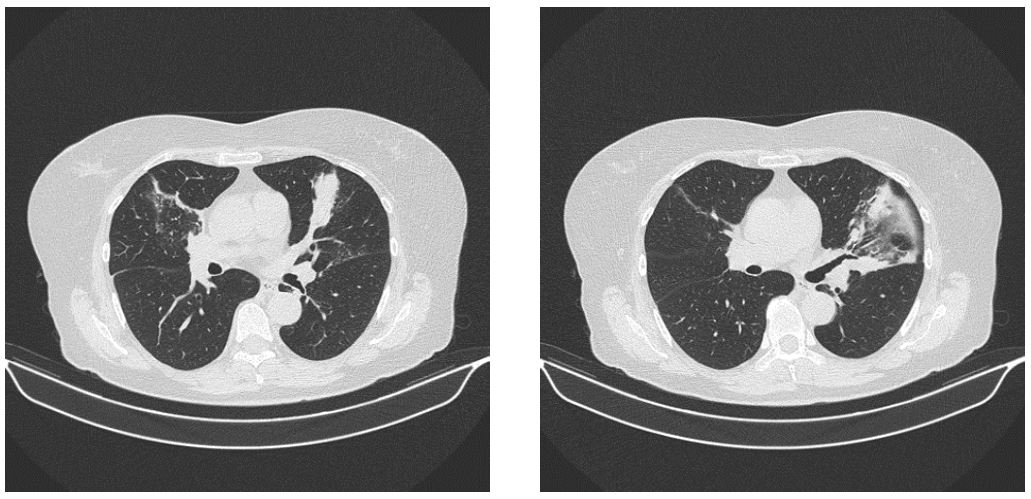

МСКТ от 03.02.2022 (рис. 1). В паренхиме легких очаговых и инфильтративных теней не выявлено. Легочной рисунок не изменен. Немногочисленные плевропульмональные спайки. Латеральные отделы S5 сегмента левого легкого уменьшены в объеме, безвоздушны, бронхи деформированы, мелкие бронхоэктазы. Пневматизация паренхимы равномерна. Средостение не расширено. Кардиоторакальный индекс < 50 %. Плотность клетчатки средостения не изменена. Трахея и бронхи свободны, стенки их не изменены. Аорта не расширена, имеет обычный ход, стенки ее не изменены. Лимфоузлы средостения не увеличены. В плевральных полостях жидкости не определяется. Мягкие ткани не изменены. Аксиальные лимфоузлы не увеличены.

Рис. 1. Пациентка Б. Компьютерная томография ОГК от 03.02.2022: на представленных компьютерных томограммах в боковом и поперечном срезах видно, что латеральные отделы S5-сегмента левого легкого уменьшены в объеме, безвоздушны, бронхи деформированы, мелкие бронхоэктазы

Заключение: очаговых и инфильтративных теней в паренхиме легких нет. Фиброателектаз латеральных отделов S5 левого легкого.